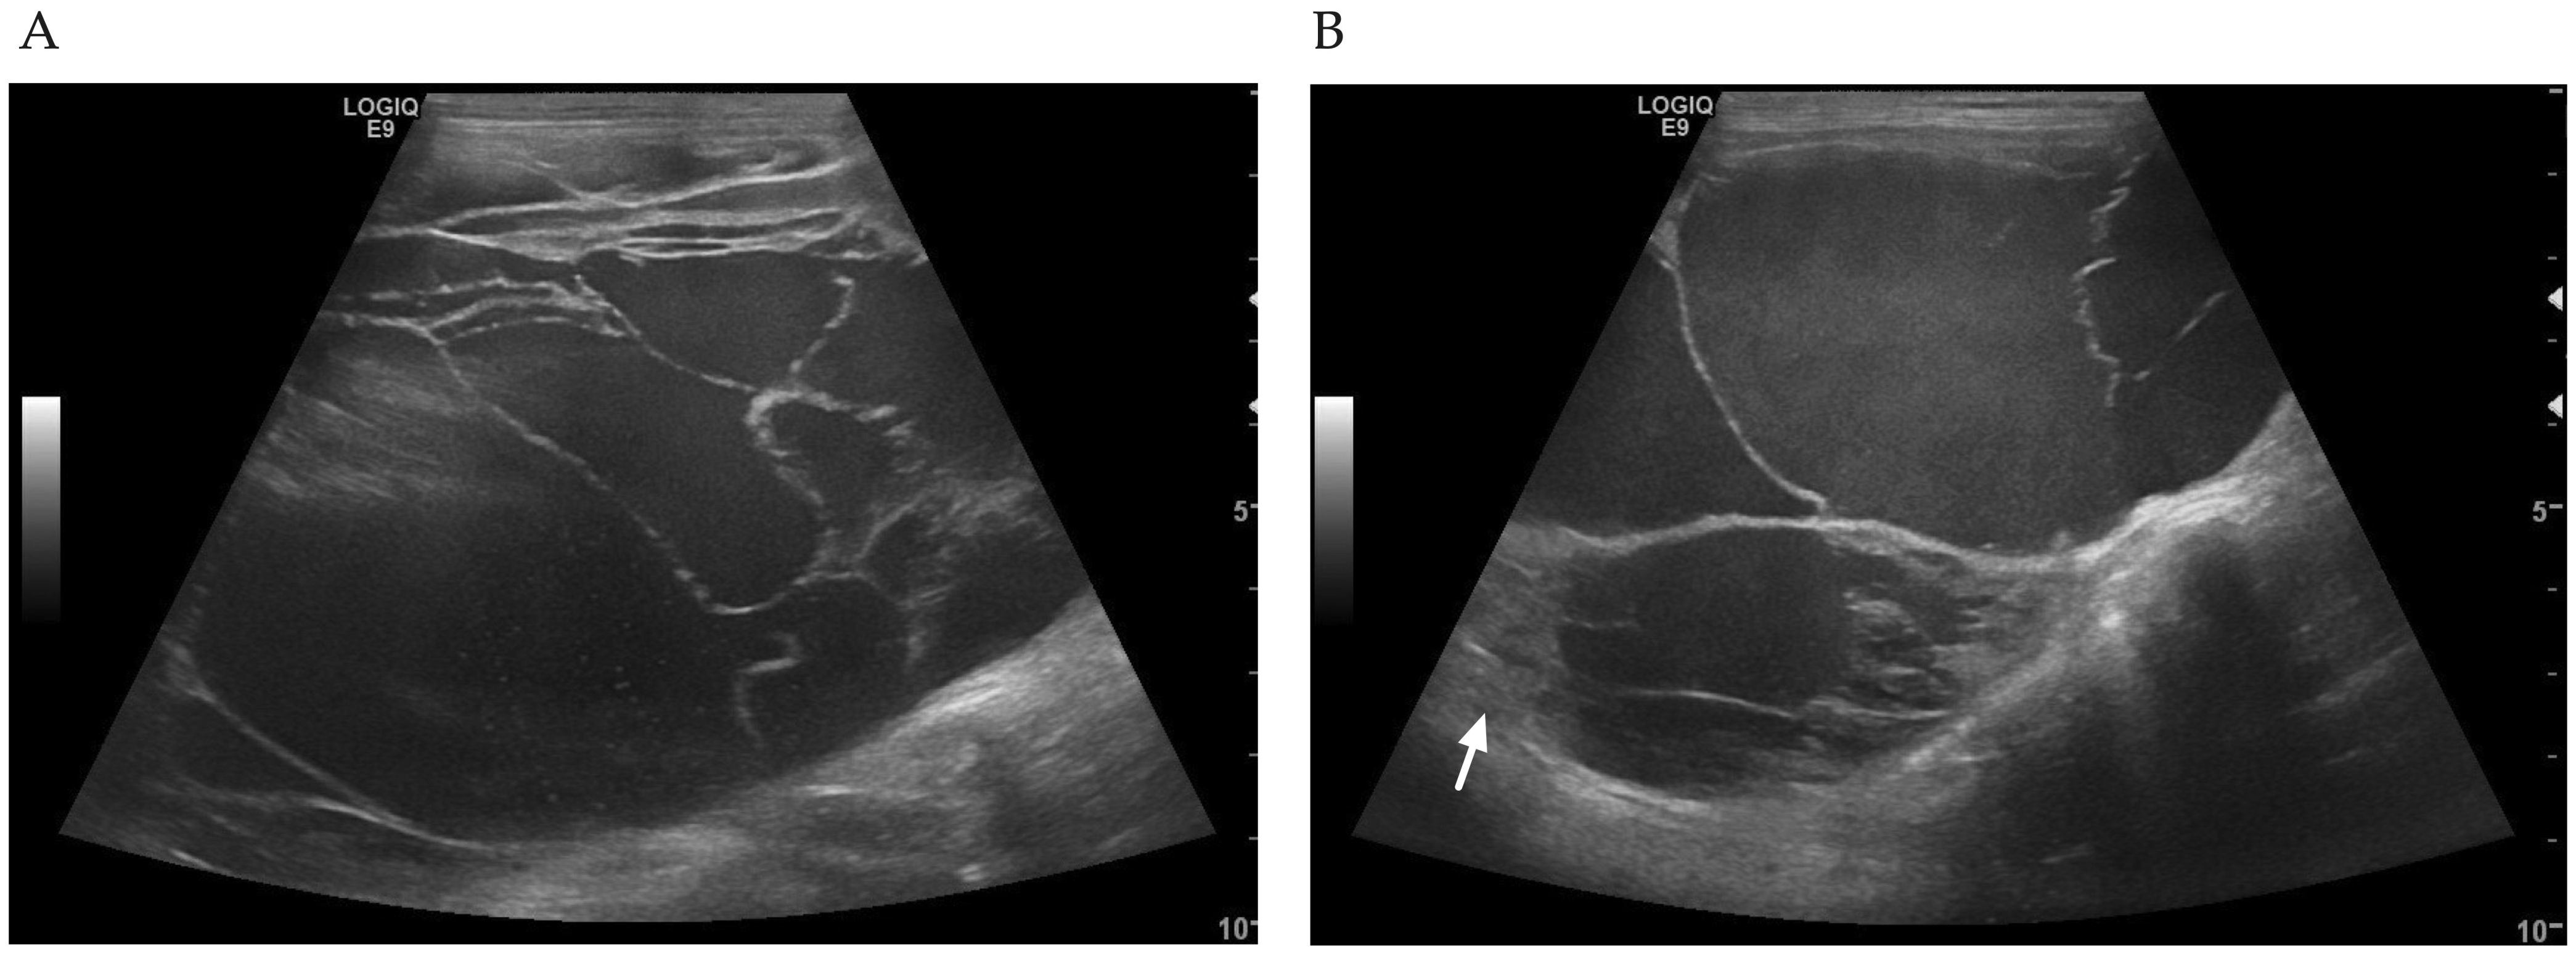

2. Case Description